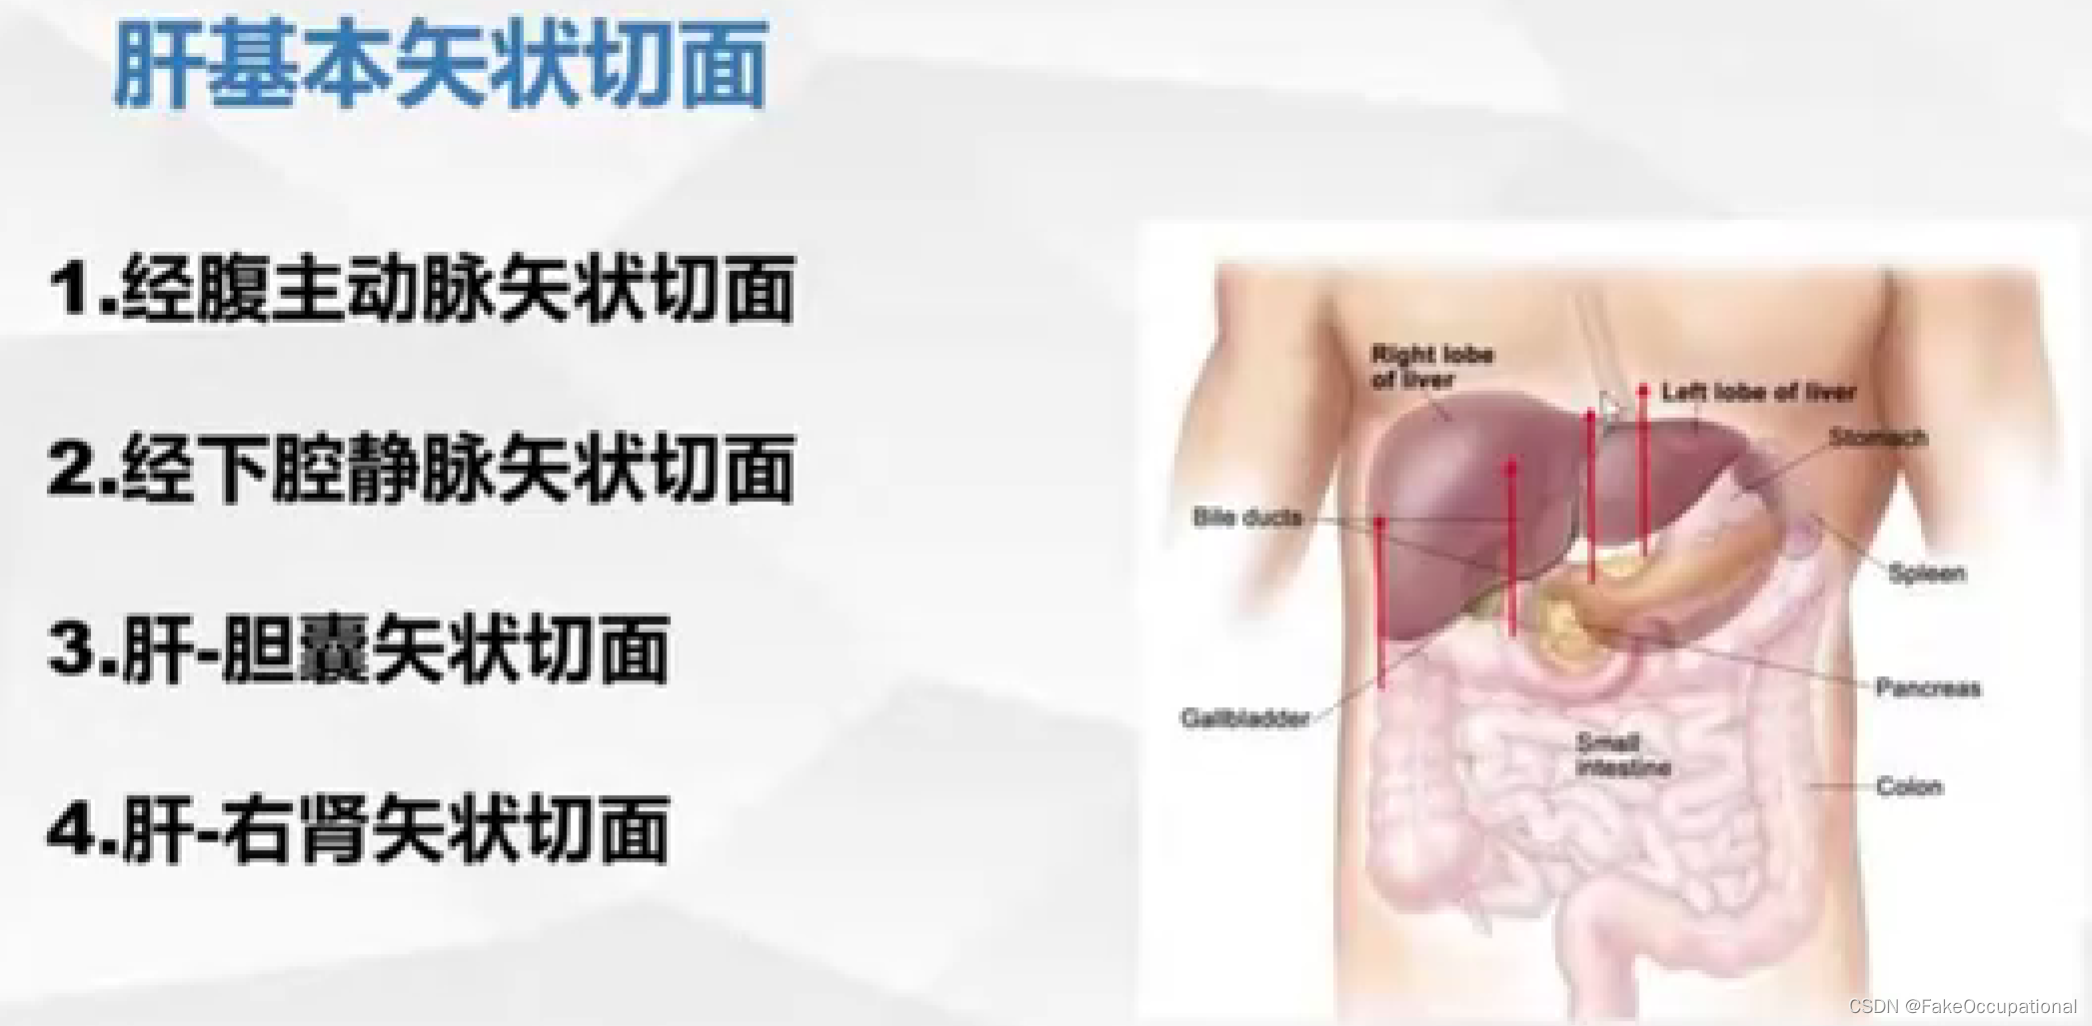

肝脏解剖概要

肝脏超声检查技术